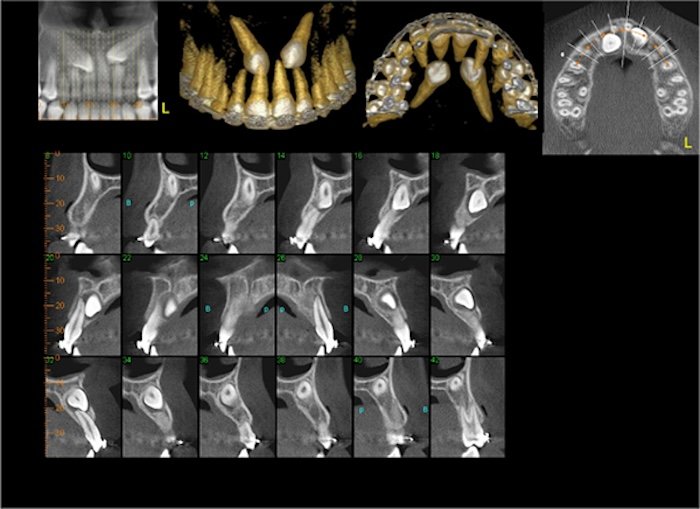

Cualquier diente de la arcada puede estar incluido. Los caninos y los premolares son los que lo hacen más frecuentemente.

El diente incluido es el que permanece dentro del hueso cuando la fecha normal de erupción dentaria se ha superado.

Una impactación dental es la detención de la erupción de un diente producida o bien por una barrera física (otro diente, hueso, quistes o encía engrosada) en el trayecto de erupción, o bien por una posición anómala del diente en el hueso alveolar desde su formación.

Estos dientes incluidos pueden causar daños irreparables a los dientes vecinos como: reabsorción de la raíz de los dientes vecinos, alteración en la posición del resto de los dientes y quistes y tumores en relación con los tejidos que originariamente formaron el diente incluido.